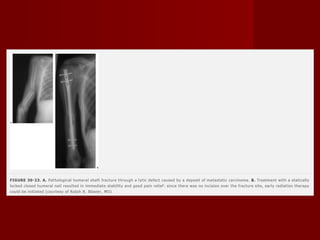

Fraturas patológicas Causa mais comum de fraturas patológicas são metástases de neoplasias malignas O osso longo mais afetado é o fêmur, seguido pelo úmero Geralmente tardiamente A perda de função pode ser muito importante em pacientes, já debilitados e podem resultar em perda de qualidade de vida. Indicação de hastes intramedulares, vantagens como mobilidade precoce, inicio rápido da radioterapia pois na há incisão,

Fraturas patológicas Causamais comum de fraturas patológicas são metástases de neoplasias malignas O osso longo mais afetado é o fêmur, seguido pelo úmero Geralmente tardiamente A perda de função pode ser muito importante em pacientes, já debilitados e podem resultar em perda de qualidade de vida. Indicação de hastes intramedulares, vantagens como mobilidade precoce, inicio rápido da radioterapia pois na há incisão,

Haste intramedular Hastes utilizadas anteriormente como pinos de Rush e hastes de Ender eram eficazes em fraturas simples, mas tinhas alguns problemas com instabilidade axial e rotacional Hastes novas com bloqueios, resolveram esses problemas, porém não apresentaram resultados tão bons como as hastes nas extremidades inferiores. Problemas com lesão no local de inserção, fraturas cominutas iatrogênicas e pseudoartrose foram observadas. Alem disso as vantagens das hastes como mobilidade precoce e diminuição de fraturas peri implantes foram ilusórias Estudos mostram uma taxa maior de reoperação e lesão de estruturas no ombro foram observadas. As indicações são fraturas patológicas, fraturas segmentar com grande diástase, lesão de partes moles

Haste intramedular Hastesutilizadas anteriormente como pinos de Rush e hastes de Ender eram eficazes em fraturas simples, mas tinhas alguns problemas com instabilidade axial e rotacional Hastes novas com bloqueios, resolveram esses problemas, porém não apresentaram resultados tão bons como as hastes nas extremidades inferiores. Problemas com lesão no local de inserção, fraturas cominutas iatrogênicas e pseudoartrose foram observadas. Alem disso as vantagens das hastes como mobilidade precoce e diminuição de fraturas peri implantes foram ilusórias Estudos mostram uma taxa maior de reoperação e lesão de estruturas no ombro foram observadas. As indicações são fraturas patológicas, fraturas segmentar com grande diástase, lesão de partes moles